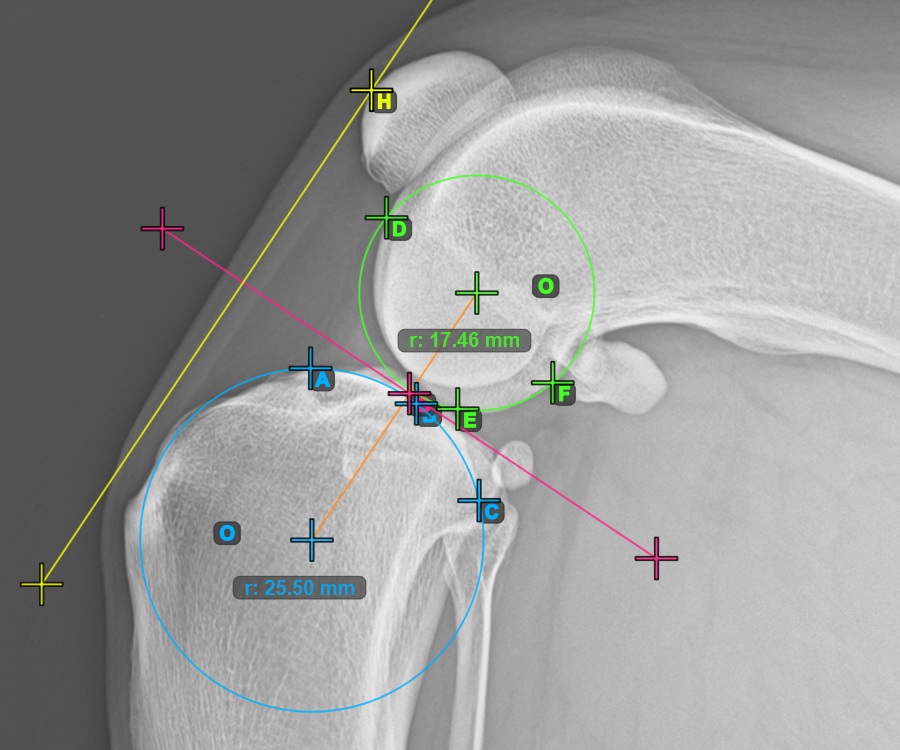

Continue by marking the three points on the articular surface of the Condylus Femoris.

Mark the three points on the main condylus of the femoral bone (Condylus Femoris). Regardless of the order, make sure to mark the most cranial point, the most caudal point and the midpoint of the Condylus Femoris. A circle will be automatically constructed based on the three placed points.

The image below represents a typical placement of the three points on the Condylus Femoris.